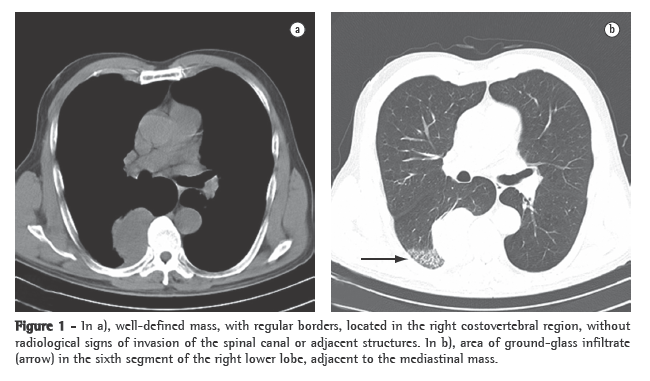

A CT scan of the chest revealed thrombosis and occlusion of the left branch of the pulmonary artery (Figure 1).

The patient was again submitted to median sternotomy involving extracorporeal circulation and total circulatory arrest, with systemic hypothermia at 18°C. Thromboendarterectomy of left branch of the pulmonary artery was performed, and exploration of the right branch revealed no thrombi (Figure 2). In addition, the thrombus was removed from the right atrium. A Greenfield inferior vena cava filter was also inserted. The duration of extracorporeal circulation was 109 min, and that of total circulatory arrest was 31 min. The patient presented favorable post-operative evolution, without complications, and was discharged from the hospital on post-operative day 5. At 59 months after the surgery, the condition of the patient was categorized as New York Heart Association functional class I, and she was under continuous treatment with warfarin. A control echocardiogram showed the pulmonary artery systolic pressure to be 40 mmHg, which remained stable over the following years, together with mild tricuspid insufficiency.